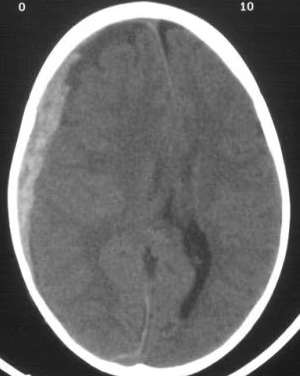

This vasculature is involved in the injury present on this CT.

What is the Middle Meningeal Artery?

This is the finding on this CT.

What is subarachnoid hemorrhage?